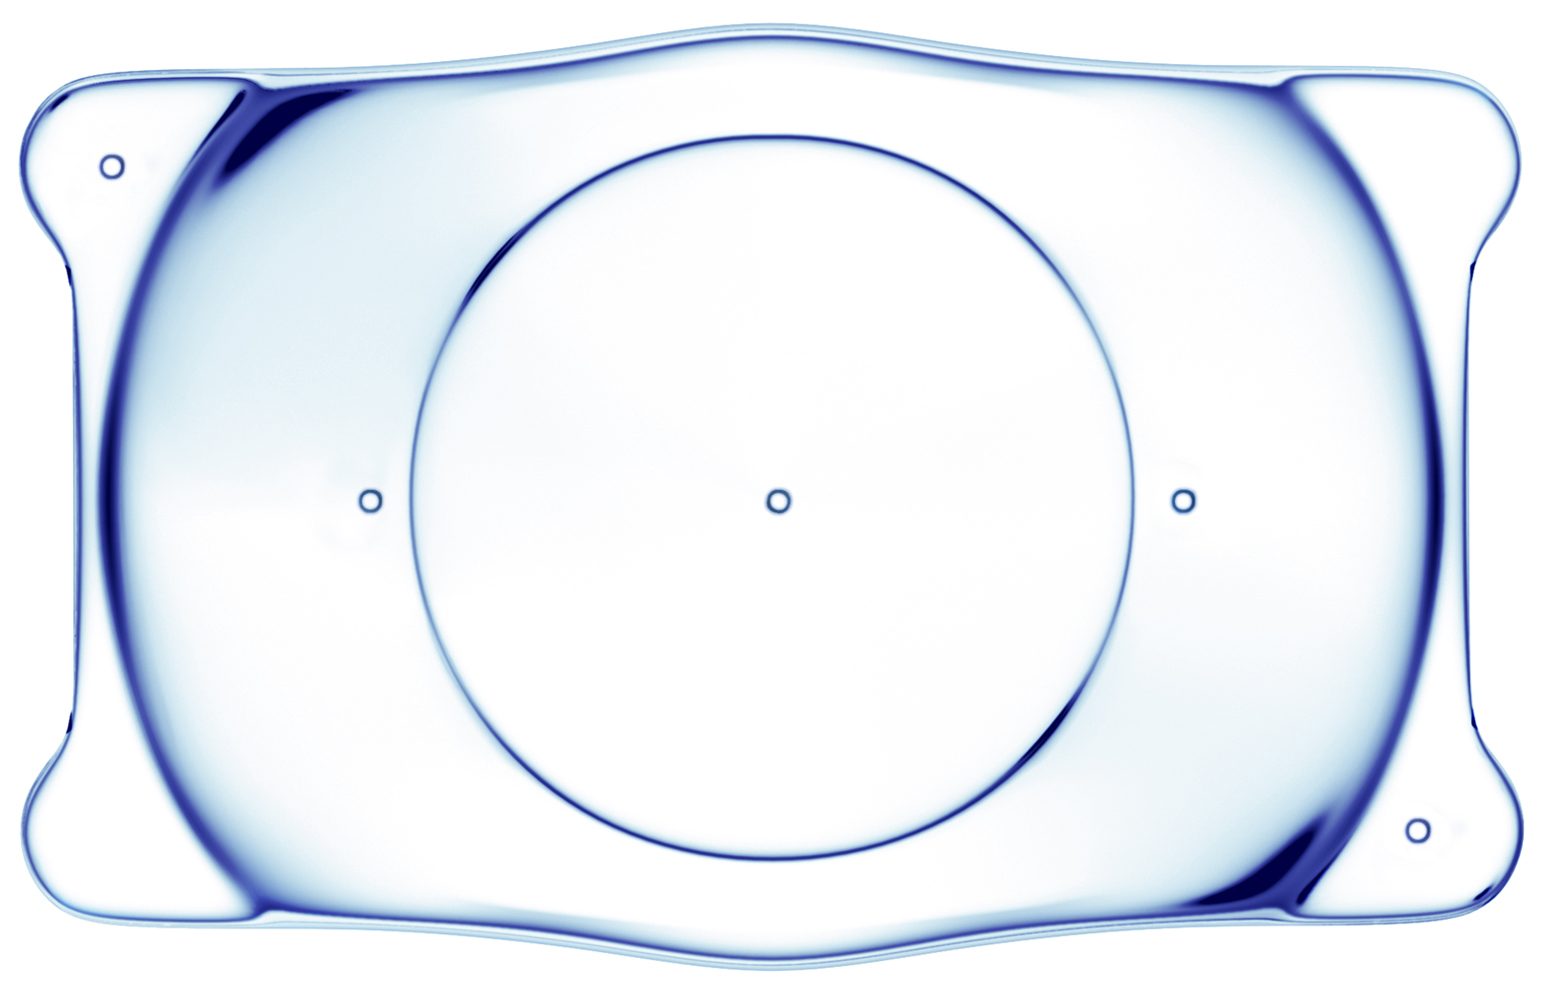

ICL晶體植入術(shù)

ICL人工晶體植入術(shù)是一種做“加法”的手術(shù),通過在眼內(nèi)植入一枚特殊的“隱形眼鏡”,從而矯正近視。安全性高,預(yù)測(cè)性好,并且手術(shù)具有可逆性、視覺質(zhì)量高,無需改變角膜形態(tài)等優(yōu)點(diǎn),是一種“可逆”的高清近視手術(shù)方式。手術(shù)后視力提升快,對(duì)角膜薄、高度、超高度近視的患者,效果尤為明顯。